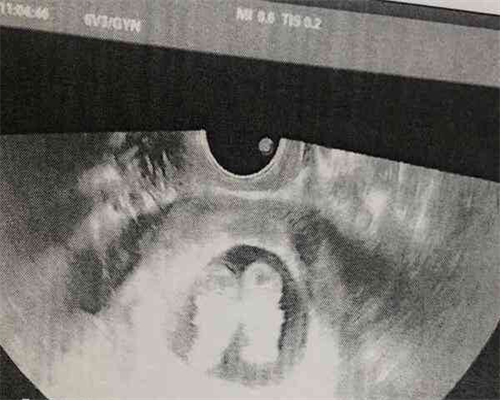

最常用的取卵方法是在局部麻醉下,在b超的引导下,将取卵针穿过穹窿至卵巢吸卵,并立即将卵移至显微镜下装有胚胎培养液的培养皿中,置于37℃培养箱中培养。取卵当天男方同时取精,取出的采用上游法或Percoll密度梯度离心法处理;